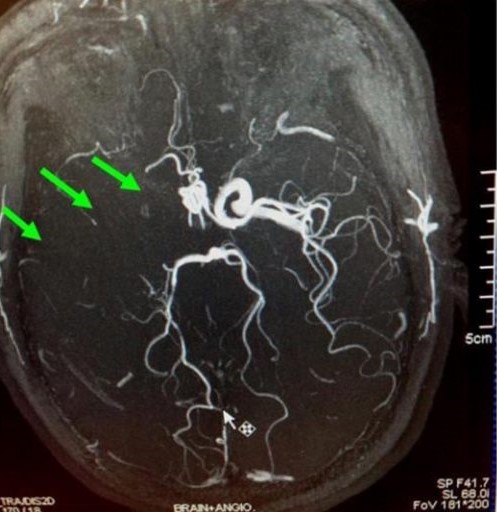

羅先生被送往私家醫院的第一步是進行緊急磁力共振造影,報告顯示羅先生右邊頸和腦部血管大動脈全部都被血栓堵塞着,右邊大腦缺血水腫,導致左邊手腳冇力和神智半昏迷。經過腦血管外科醫生的診斷和急救,在全身麻醉下,醫生使用尤如髪絲微細的導管,經過病人右邊大腿的腹股溝的大動脈而入,導管再經過腹部和胸腔的大動脈一直向上,遊走到病人右邊的頸和腦部血管大動脈,進行機械式血栓吸取內血管治療急救。